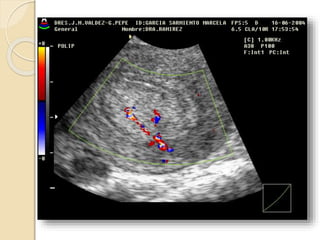

POLIPO ENDOMETRIAL

Se forman por una proliferación

anómala focal o multifocal de la capa

basal del endometrio y del estroma.

Son mas sensibles al estímulo

estrogénico y por esto es frecuente que

coexistan con una hiperplasia

endometrial.

Pueden ser sésiles o pediculados, únicos o múltiples y de

tamaño variable.

Suelen ser hiperecogénicos y en su espesor pueden

apreciarse pequeñas imágenes econegativas quísticas de

diferente tamaño.

Con la ayuda del Doppler color podemos identificar el

pedículo vascular.

La histerosonografía diagnóstica con nitidez la existencia

de pólipos endometriales. Incluidos los de dimensiones

reducidas, su numero, localización, su inserción y las

características del endometrio adyacente.

POLIPO ENDOMETRIAL Seforman por una proliferación anómala focal o multifocal de la capa basal del endometrio y del estroma. Son mas sensibles al estímulo estrogénico y por esto es frecuente que coexistan con una hiperplasia endometrial.

POLIPO ENDOMETRIAL Puedenser sésiles o pediculados, únicos o múltiples y de tamaño variable. Suelen ser hiperecogénicos y en su espesor pueden apreciarse pequeñas imágenes econegativas quísticas de diferente tamaño. Con la ayuda del Doppler color podemos identificar el pedículo vascular. La histerosonografía diagnóstica con nitidez la existencia de pólipos endometriales. Incluidos los de dimensiones reducidas, su numero, localización, su inserción y las características del endometrio adyacente.